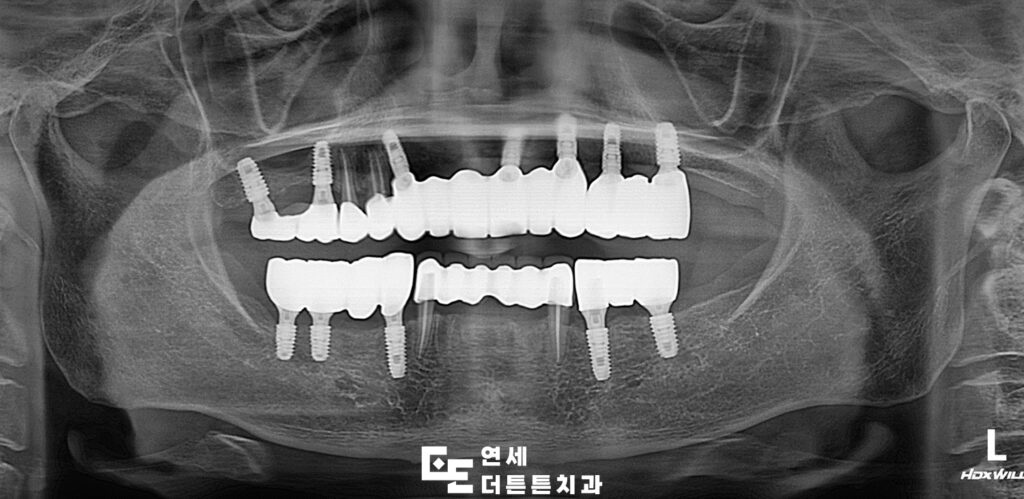

기능과 심미성을 함께 고려하여

최종 보철물 장착까지 마무리된 상태입니다.

방학역치과 환자분께서는 치료 이후 식사가 한결 편해졌고

외관적인 부분도 자연스럽게 회복되어

만족스럽다는 반응을 보이셨습니다.

이처럼 전체 임플란트 치료는 기능과 심미성을

동시에 개선하는 데 도움이 될 수 있습니다.